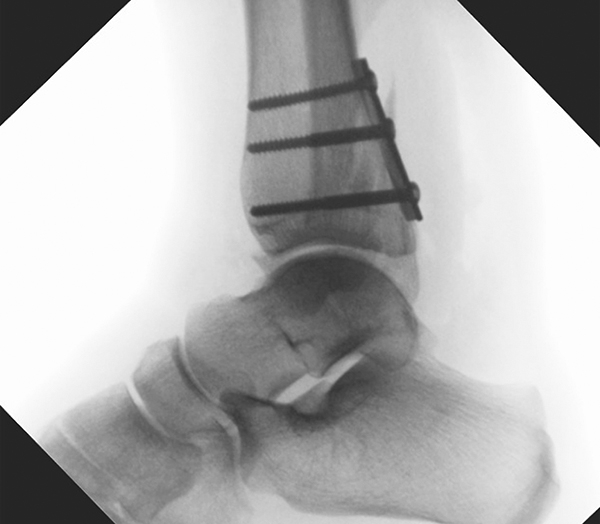

Die Versorgung von AO 44-B Frakturen erfolgt über einen längsverlaufenden lateralen Zugang. In der Regel gelingt eine suffiziente Stabilisierung mittels interfragmentärer Zugschraube (bei langem Frakturverlauf ggf. 2 Zugschrauben) und einer zusätzlichen Neutralisationsplatte (Abbildung 9 & 10).

Bei multifragmentären Frakturen (AO 44-B2.3) oder bei schlechter Knochenqualität sollte die Versorgung mittels winkelstabiler Plattenosteosynthese erwogen werden (Abbildung 11 & 12).